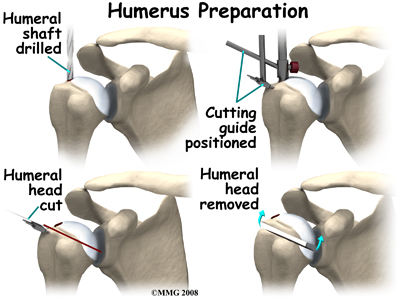

At this point, the surgeon can prepare the bone for attaching the replacement parts. The ball portion of the humeral head is removed with a bone saw. The hollow inside of the upper humerus is prepared using a rasp, which allows your surgeon to mold the space in order to anchor the metal stem of the humeral component inside the bone.